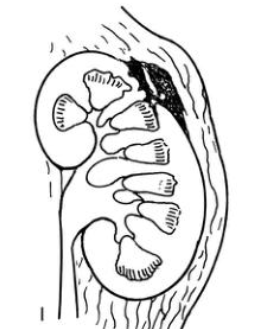

Pierwszy stopień uszkodzenia nerki

Stłuczenie, krwiak podtorebkowy

Drugi stopień uszkodzenia nerki

Krwiak okołonerkowy lub rozdarcie miąższu <1cm